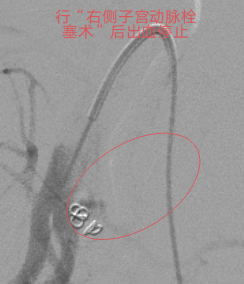

本着“生命至上”的原则,吴主任立即启动介入导管室为产妇施行“造影术”检查,造影发现产妇子宫动脉远端均有活动性出血,尤以左侧子宫动脉出血明显,血液不断外渗,病情紧急,止血治疗迫在眉睫!要知道产后大出血是非常凶险的疾病,不能有效止血可能需要切除子宫保命的!但患者才不到三十岁呀,正值青春年华,切除子宫对患者以后可是有非常大的影响。此时,能及时止血救命,又能保住子宫的微创介入止血法的优势就出来了!在患者及其家属的期盼和高度信任下,吴主任顺利为患者施行微创介入止血手术,术后患者子宫动脉出血停止,阴道出血减少,术后无需继续输血血压、血红蛋白均能维持稳定。术后经常规产后康复护理治疗后,患者病情稳定,没有异常阴道出血,现已康复出院。

血管造影见

双侧子宫动脉出血

行微创介入止血手术后出血停止